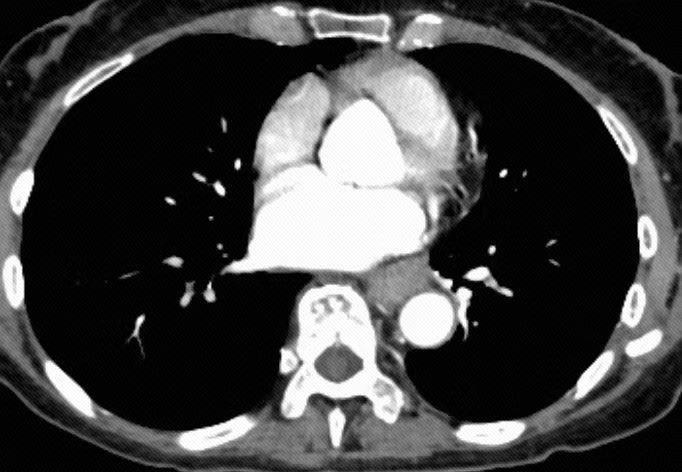

譚阿姨(化名)今年69歲,近兩個月來反覆出現吞咽困難,嚴重影響日常生活,經親友介紹來到深圳市第二人民醫院胸外科就診。入院後,經全面系統檢查,患者被確診為食管胸中段鱗狀細胞癌(cT2N2M0 G1 ⅢA 期)。術前分期提示腫瘤已處於局部晚期,治療難度顯著增加。更為複雜的是,患者合併高血壓、高血脂等多年基礎疾病,長期服用相關藥物,身體條件較差,為食管癌診療帶來多重挑戰。

團隊首先採用「抗PD-1(免疫檢查點抑制劑)+化療」方案,完成2個周期的新輔助治療。該方案旨在術前縮小腫瘤體積、降低腫瘤分期、清除微小轉移病灶,為後續根治性手術創造有利條件。治療後復查評估顯示,患者腫瘤達到部分緩解(PR),療效顯著,為順利開展手術奠定了堅實基礎。